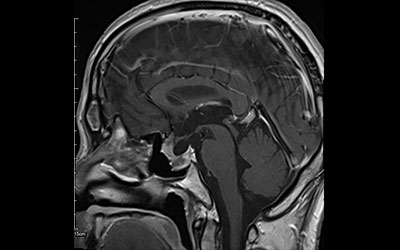

鼻の孔から内視鏡を挿入し脳腫瘍の摘出を行なう手術です。最新最高性能のメドトロニック社製磁場式ナビゲーションシステムを用いて、顔、口腔内、頭皮を傷つけることなく脳内の手術を実施しています。

手術後(3ヶ月後)